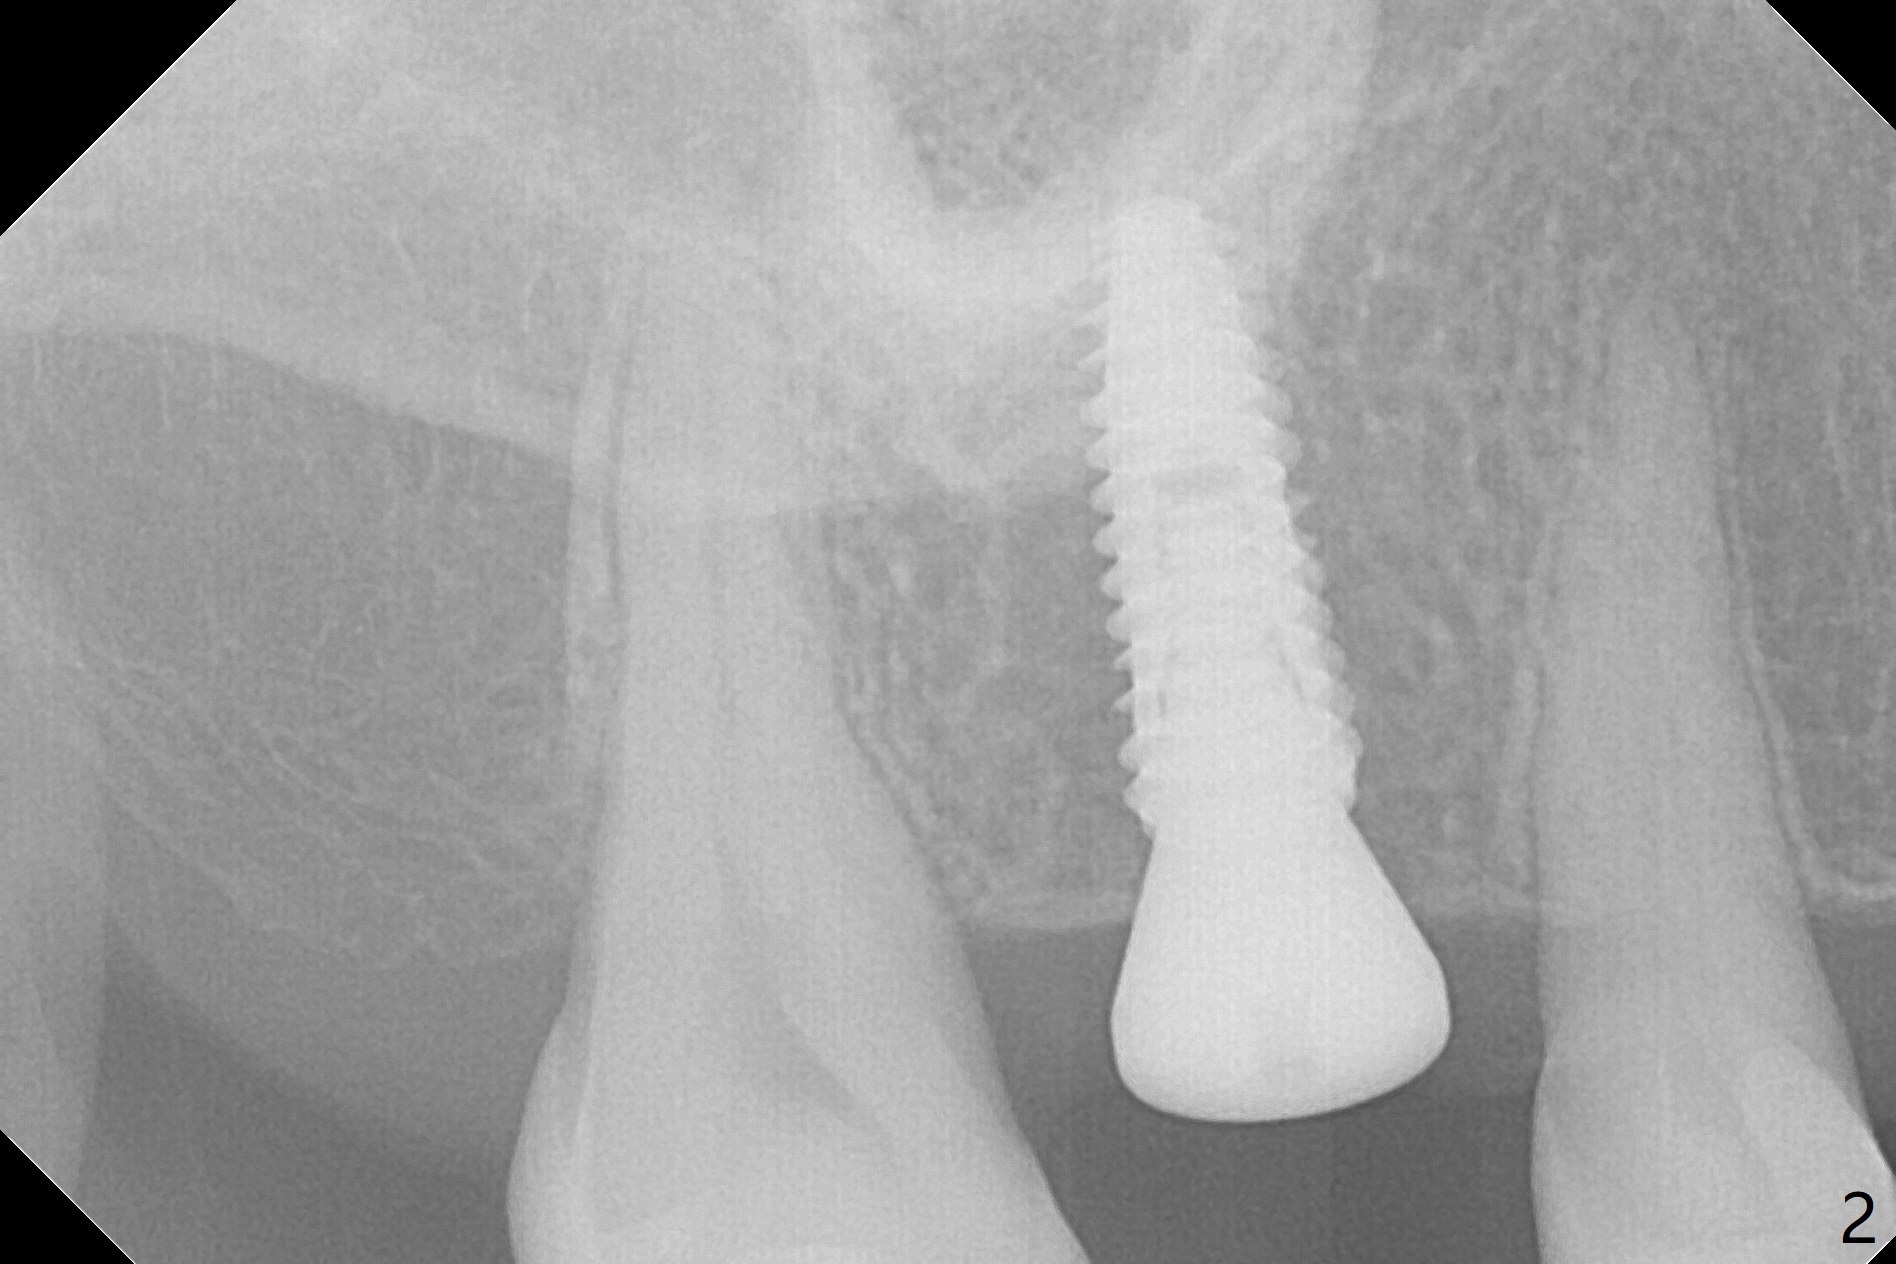

With understanding tissue punch and engagement of drill as much as possible into guide sleeve before pressing pedal, guided surgery is accomplished with confidence (Fig.1,2).  With undersized drilling, there is no thread exposure palatally, when a flap is raised.  Vanilla graft is placed, since it has been prepared before incision.  No membrane is used.  It appears that the palatal bone expands while the implant is being placed.  CBCT taken 10 days postop shows apparently the coronal end of the palatal plate (Fig.3 arrows) and bone graft (<).  Although postop pain is slightly more associated with incision for bone graft, the wound heals with periodontal dressing 10 days postop.